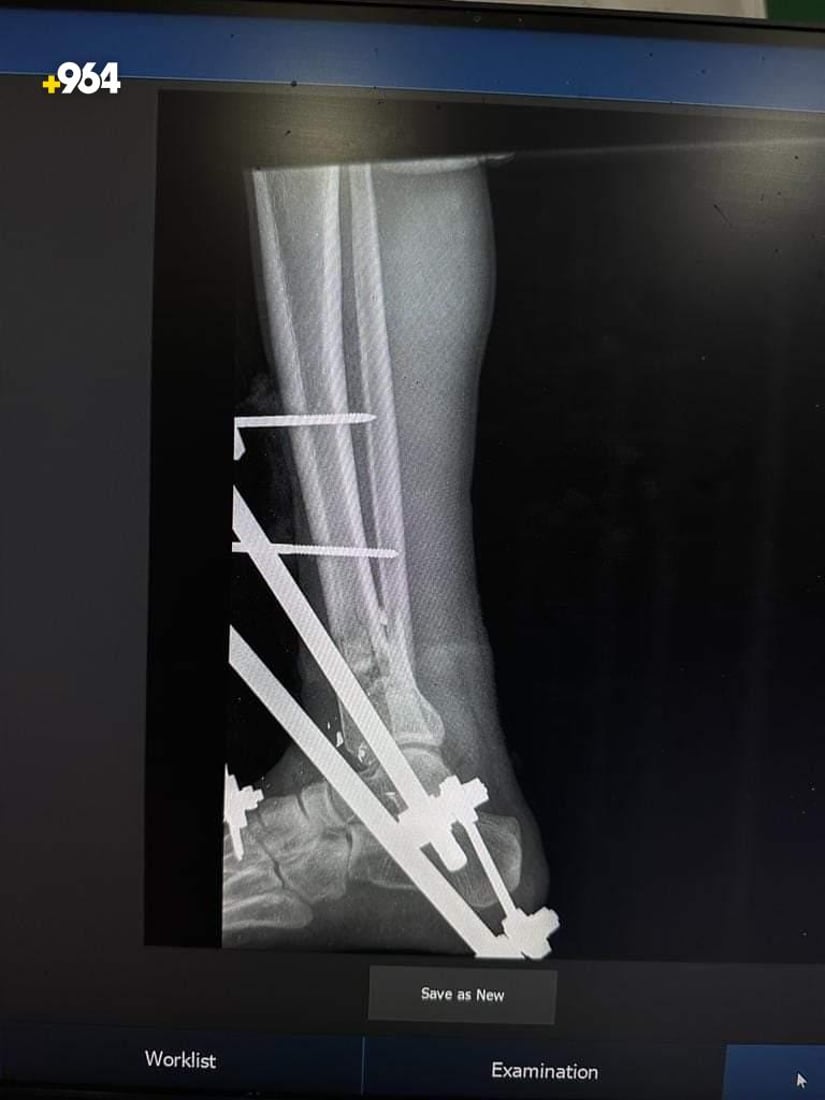

صور: أطباء ينجحون في تثبيت كسر مضاعف أسفل الساق لمصاب في تلعفر

نجح فريق طبي في مستشفى بلدة تلعفر العام بنينوى، اليوم الاثنين، من تثبيت كسر أسفل عظم الساق لشاب، بعد عملية جراحية نادرة، وفقاً لإدارة المستشفى.

تمكّن فريق طبي متخصص في قسم جراحة العظام والكسور بمستشفانا من إجراء عملية معقدة لشاب في السابعة عشرة من العمر، كان يعاني من كسر في الساق.

الفريق الذي ترأسه الدكتور زكريا ربيع، اكتشف نتيجة الفحوصات أن الشاب يعاني من كسر مضاعف أسفل عظم الساق الأيسر، إلى جانب جرح تهتكي وفقدان في الانسجة الرخوة.

الفريق نجح في تثبيت الكسر بالمثبت الخارجي بعد إجراء الإسعافات الأولية.